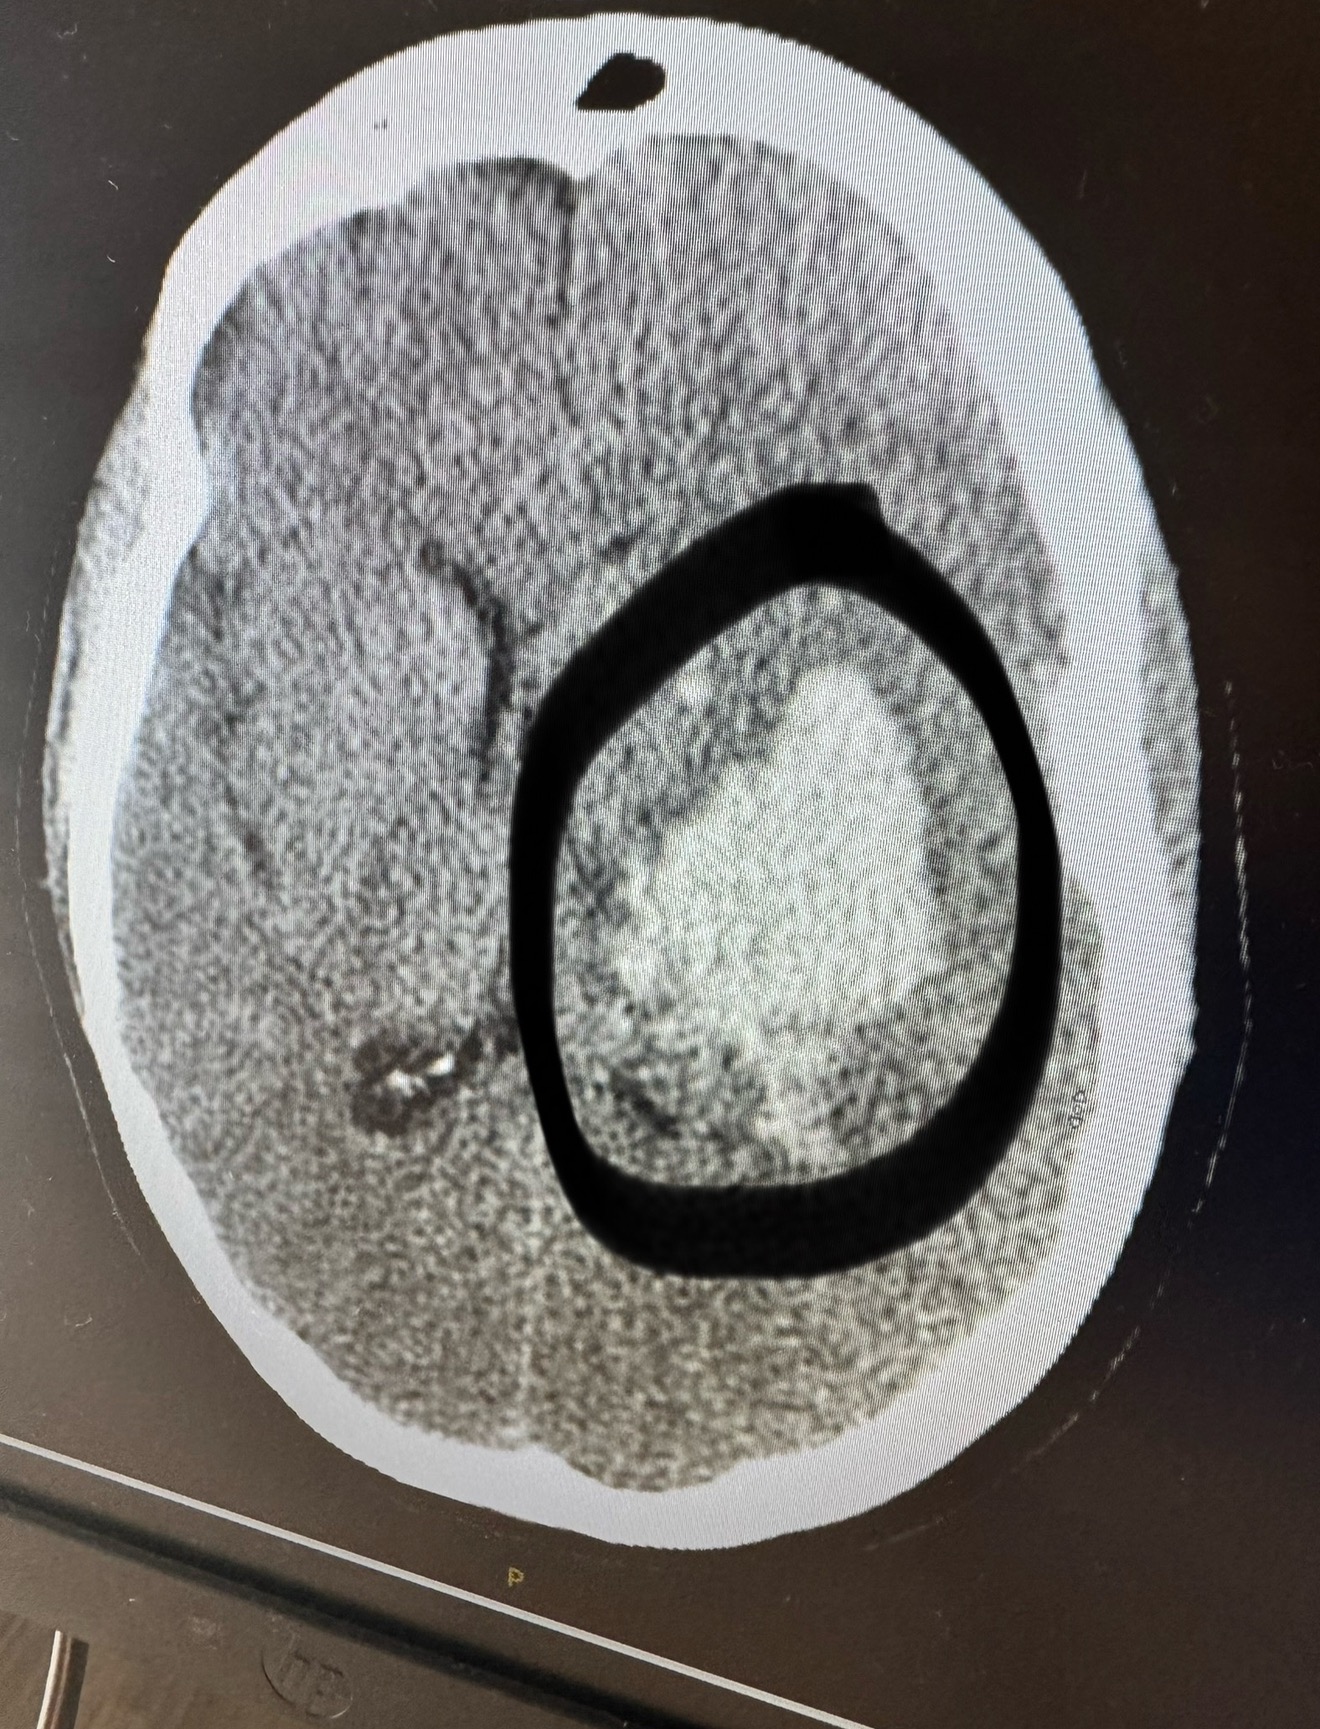

Hi everyone! My name is Billy Coble and I’m starting this GoFundMe for my little sister and her son. Teresa Coble is 43 years old and a retired Army veteran. Last week, she suffered a major stroke and is still in the ICU. She is unable to speak, has partial paralysis on her left side, and almost complete paralysis on the right.